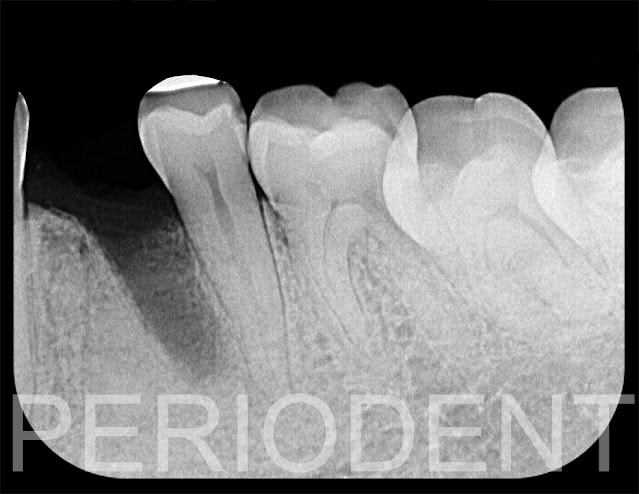

1. 患者第一小臼齒傾斜緊靠第二小臼齒,而且已經牙根斷裂